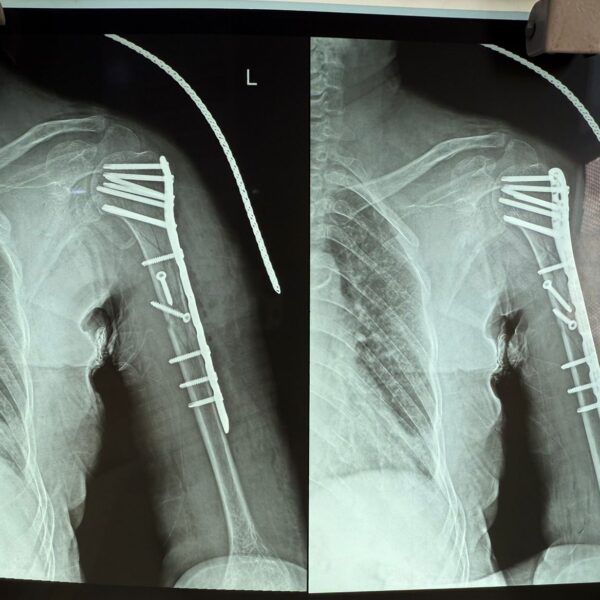

Moments That Mark Meaningful Recovery

Witness real patient transformations at The Ortho Clinic through images that reflect successful treatments and restored mobility.